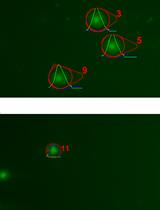

视觉刺激四臂迷宫测试评估小鼠的认知和视觉

Visual-stimuli Four-arm Maze test to Assess Cognition and Vision in Mice

JV Jean-Philippe Vit

DF Dieu-Trang Fuchs

AA Ariel Angel

AL Aharon Levy

IL Itschak Lamensdorf

KB Keith L. Black

YK Yosef Koronyo

MK Maya Koronyo-Hamaoui

5305 Views

Nov 20, 2021

Visual impairments, notably loss of contrast sensitivity and color vision, were documented in Alzheimer’s disease (AD) patients yet are critically understudied. This protocol describes a novel visual-stimuli four-arm maze (ViS4M; also called visual x-maze), which is a versatile x-shaped maze equipped with spectrum- and intensity-controlled light-emitting diode (LED) sources and dynamic grayscale objects. The ViS4M is designed to allow the assessment of color and contrast vision along with locomotor and cognitive functions in mice. In the color testing mode, the spectral distributions of the LED lights create four homogenous spaces that differ in chromaticity and luminance, corresponding to the mouse visual system. In the contrast sensitivity test, the four grayscale objects are placed in the middle of each arm, contrasting against the black walls and the white floors of the maze. Upon entering the maze, healthy wild-type (WT) mice tend to spontaneously alternate between arms, even under equiluminant conditions of illumination, suggesting that cognitively and visually intact mice use both color and brightness as cues to navigate the maze. Evaluation of the double-transgenic APPSWE/PS1ΔE9 mouse model of AD (AD+ mice) reveals substantial deficits to alternate in both color and contrast modes at an early age, when hippocampal-based memory and learning is still intact. Profiling of timespan, entries, and transition patterns between the different arms uncovers variable aging and AD-associated impairments in color discrimination and contrast sensitivity. The analysis of arm sequences of alternation reveals different pathways of exploration in young WT, old WT, and AD+ mice, which can be used as color and contrast imprints of functionally intact versus impaired mice. Overall, we describe the utility of a novel visual x-maze test to identify behavioral changes in mice related to cognition, as well as color and contrast vision, with high precision and reproducibility.Graphic abstract: Exploratory behavior of AD+ mice versus age- and sex-matched WT mice is tracked (top left: trajectory from a 5-min video file) in a novel visual-stimuli four-arm maze (ViS4M; also named visual x-maze) equipped with spectrum- and intensity-controlled LED sources or grayscale objects. Consecutive arm entries reveal that APPSWE/PS1ΔE9 (AD+) mice alternate less between arms, as opposed to WT mice. Sequence analysis, according to the three alternation pathways (depicted by white, yellow, and brown arrows) under different conditions of illumination, uncovers specific deficits linked to color vision in AD+ mice, evidenced by a color imprint chart.